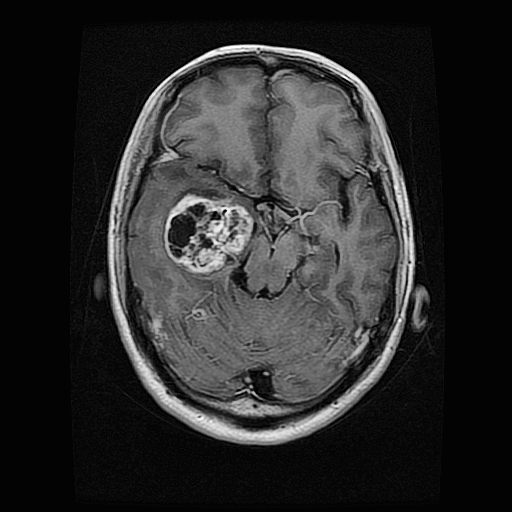

Brain Tumor 脑肿瘤数据集

该数据集是一个脑肿瘤 MRI 分割与分类数据集,旨在为脑肿瘤的医学影像分析提供高质量数据支撑,适用于脑肿瘤分割和分类任务。数据包含约 5,000 张 MRI 切片,其中:

- 无肿瘤(No Tumor):约 1,200 例

- 神经胶质瘤(Glioma):约 1,300 例

- 脑膜瘤(Meningioma):约 1,250 例

- 垂体瘤(Pituitary):约 1,250 例

- 带分割掩码数据:约 2,700 例